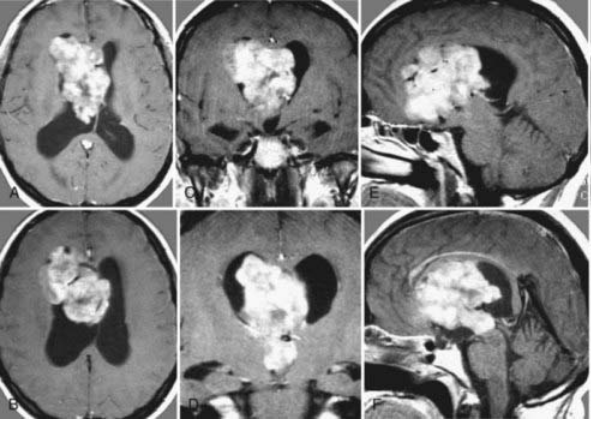

术前MRI

血管丰富的巨大肿瘤全切、无神经功能障碍

术中证实为一实质性、血供丰富的室管膜下瘤,经显微手术完全切除,术后MRI证实肿瘤全切,患者术后无神经功能障碍及其他并发症。